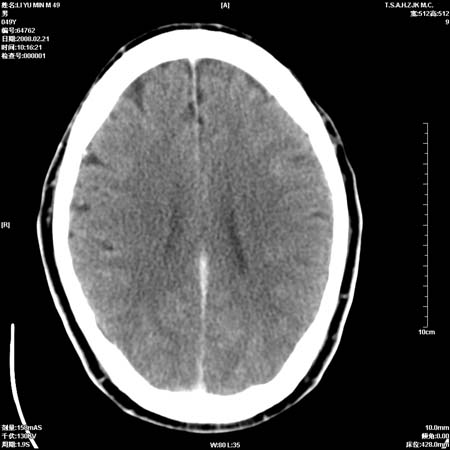

男性, 49岁, 头痛, 行ct检查后, 我科一名大夫报了蛛网膜下腔出血, 请大家讨论!

大脑纵裂池及鞍上池应该有蛛血